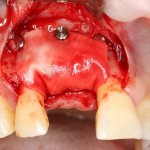

Другой вариант. Имплантируем, но существующего объема костной ткани недостаточно для получения адекватного эстетического и функционального результата:

Поэтому мы используем мембрану Geistlich BioGide и всё ту же аутокостную стружку:

Вот чем мне нравится мембрана BioGide — так это своими свойствами. Предсказуема до мелочей.

Во влажном состоянии она эластична и податлива, поэтому нет необходимости использовать пины или винты: